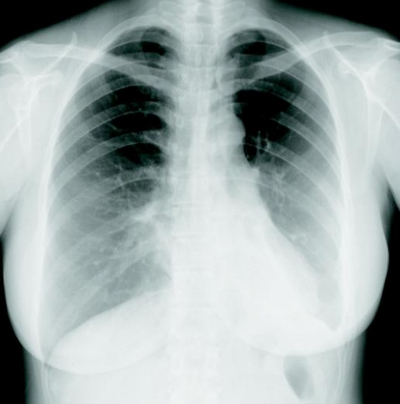

現症 : 意識レベルは JCSⅠ-1、GCS 15(E4V5M6) 。身長 155 cm、体重 48 kg。体温 37.2 ℃。脈拍 112/分、整。血圧 78/40 mmHg。呼吸数 28/分。SpO₂ 94%(room air) 。頸部リンパ節に腫脹を認めない。心音に異常を認めない。呼吸音は左下胸部で減弱し、coarse crackles を聴取する。腹部は平坦、軟で、肝・脾を触知しない。腹部の手術創部に異常を認めない。背部に叩打痛を認めない。両下腿に浮腫を認める。

検査所見 : 血液所見:赤血球 388 万、Hb 11.2 g/dL、Ht 36 %、白血球 9,800(桿状核好中球 39 %、分葉核好中球 45 %、好酸球3%、好塩基球2%、単球4%、リンパ球7% )、血小板 18 万、D ダイマー 3.4 μg/mL(基準 1.0 以下)。血液生化学所見:総蛋白 6.5 g/dL、アルブミン 2.9 g/dL、尿素窒素 21 mg/dL、クレアチニン1.2 mg/dL、Na 139 mEq/L、 K 4.1 mEq/L、 Cl 108 mEq/L。 CRP 12 mg/dL、乳酸 14 mg/dL(基準5〜20)。胸部エックス線写真を別に示す。血液培養セットから Klebsiella pneumoniae が検出された。